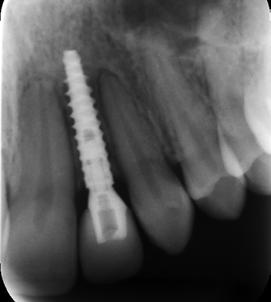

6. ábra: Egy 3 mm átmérőjű implantátum optimális pozíciójának vizsgálata keresztirányú felvételen. (Az 1. ábrán bemutatott eset.)

12. ábra: Radiológiai felvétel a csontpótlás után. Hasonlítsuk össze a 6. ábrával!

18. ábra: Radiológiai felvétel a csontpótlást követően 5 hónappal behelyezett 3 mm átmérőjú NobelActive implantátumról és 15°os szögtört felépítményről.